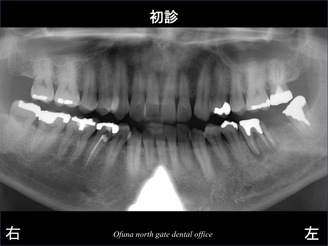

下顎の左側の奥歯が折れていたのです。

以下のレントゲン写真の赤丸が歯根破折 しているのです。

それでは、分かりやすくするために赤丸の部分を拡大してみます。

奥の根が折れているのが分かるかと思います。